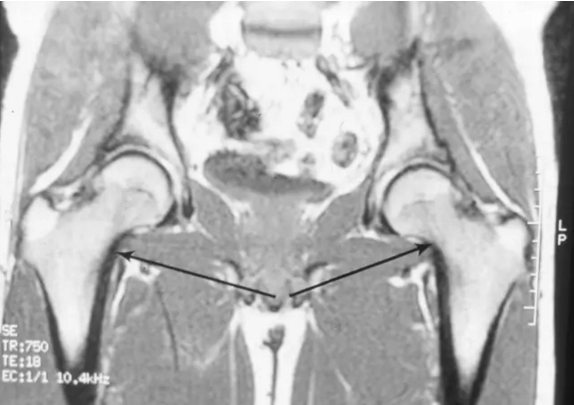

股骨头缺血坏死

轻度扁平至左股骨头的上方(空心箭头)表示第3期疾病。 右股骨头具有正常的轮廓,表明阶段2疾病。 黑色箭头表示修复区的边缘,代表死亡小梁上的新骨形成。 双侧的AVN,它通常发生在不同时间的每个髋部,并且疾病在每个髋部的分期可以,并且经常是,在不同的阶段。